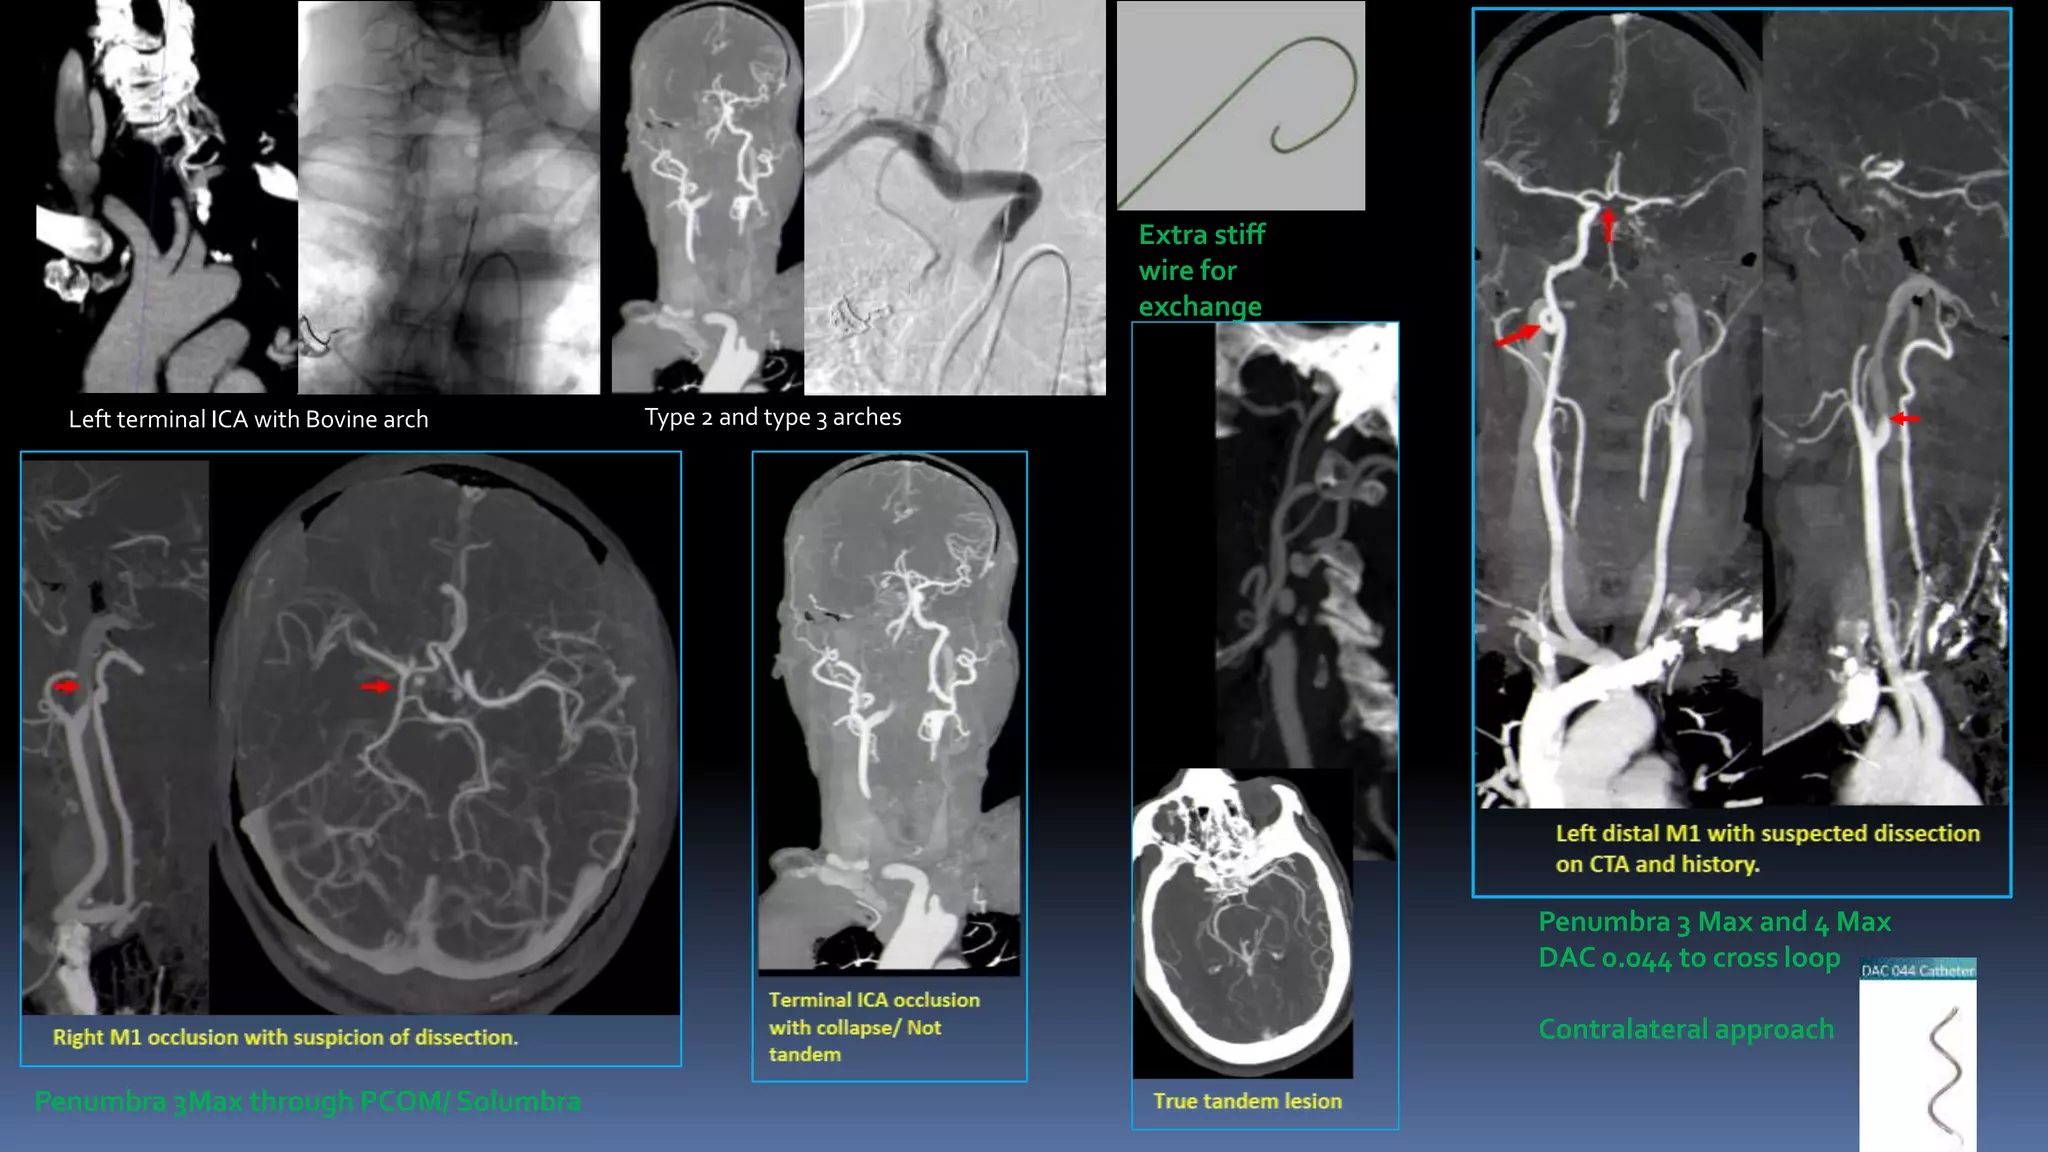

Left terminal ICA with Bovine arch Type 2 and type 3 arches

Extra stiff

wire for

exchange

Penumbra 3 Max and 4 Max

DAC 0.044 to cross loop

Contralateral approach

Penumbra 3Max through PCOM/ Solumbra

Left terminal ICAwith Bovine arch Type 2 and type 3 arches Extra stiff wire for exchange Penumbra 3 Max and 4 Max DAC 0.044 to cross loop Contralateral approach Penumbra 3Max through PCOM/ Solumbra